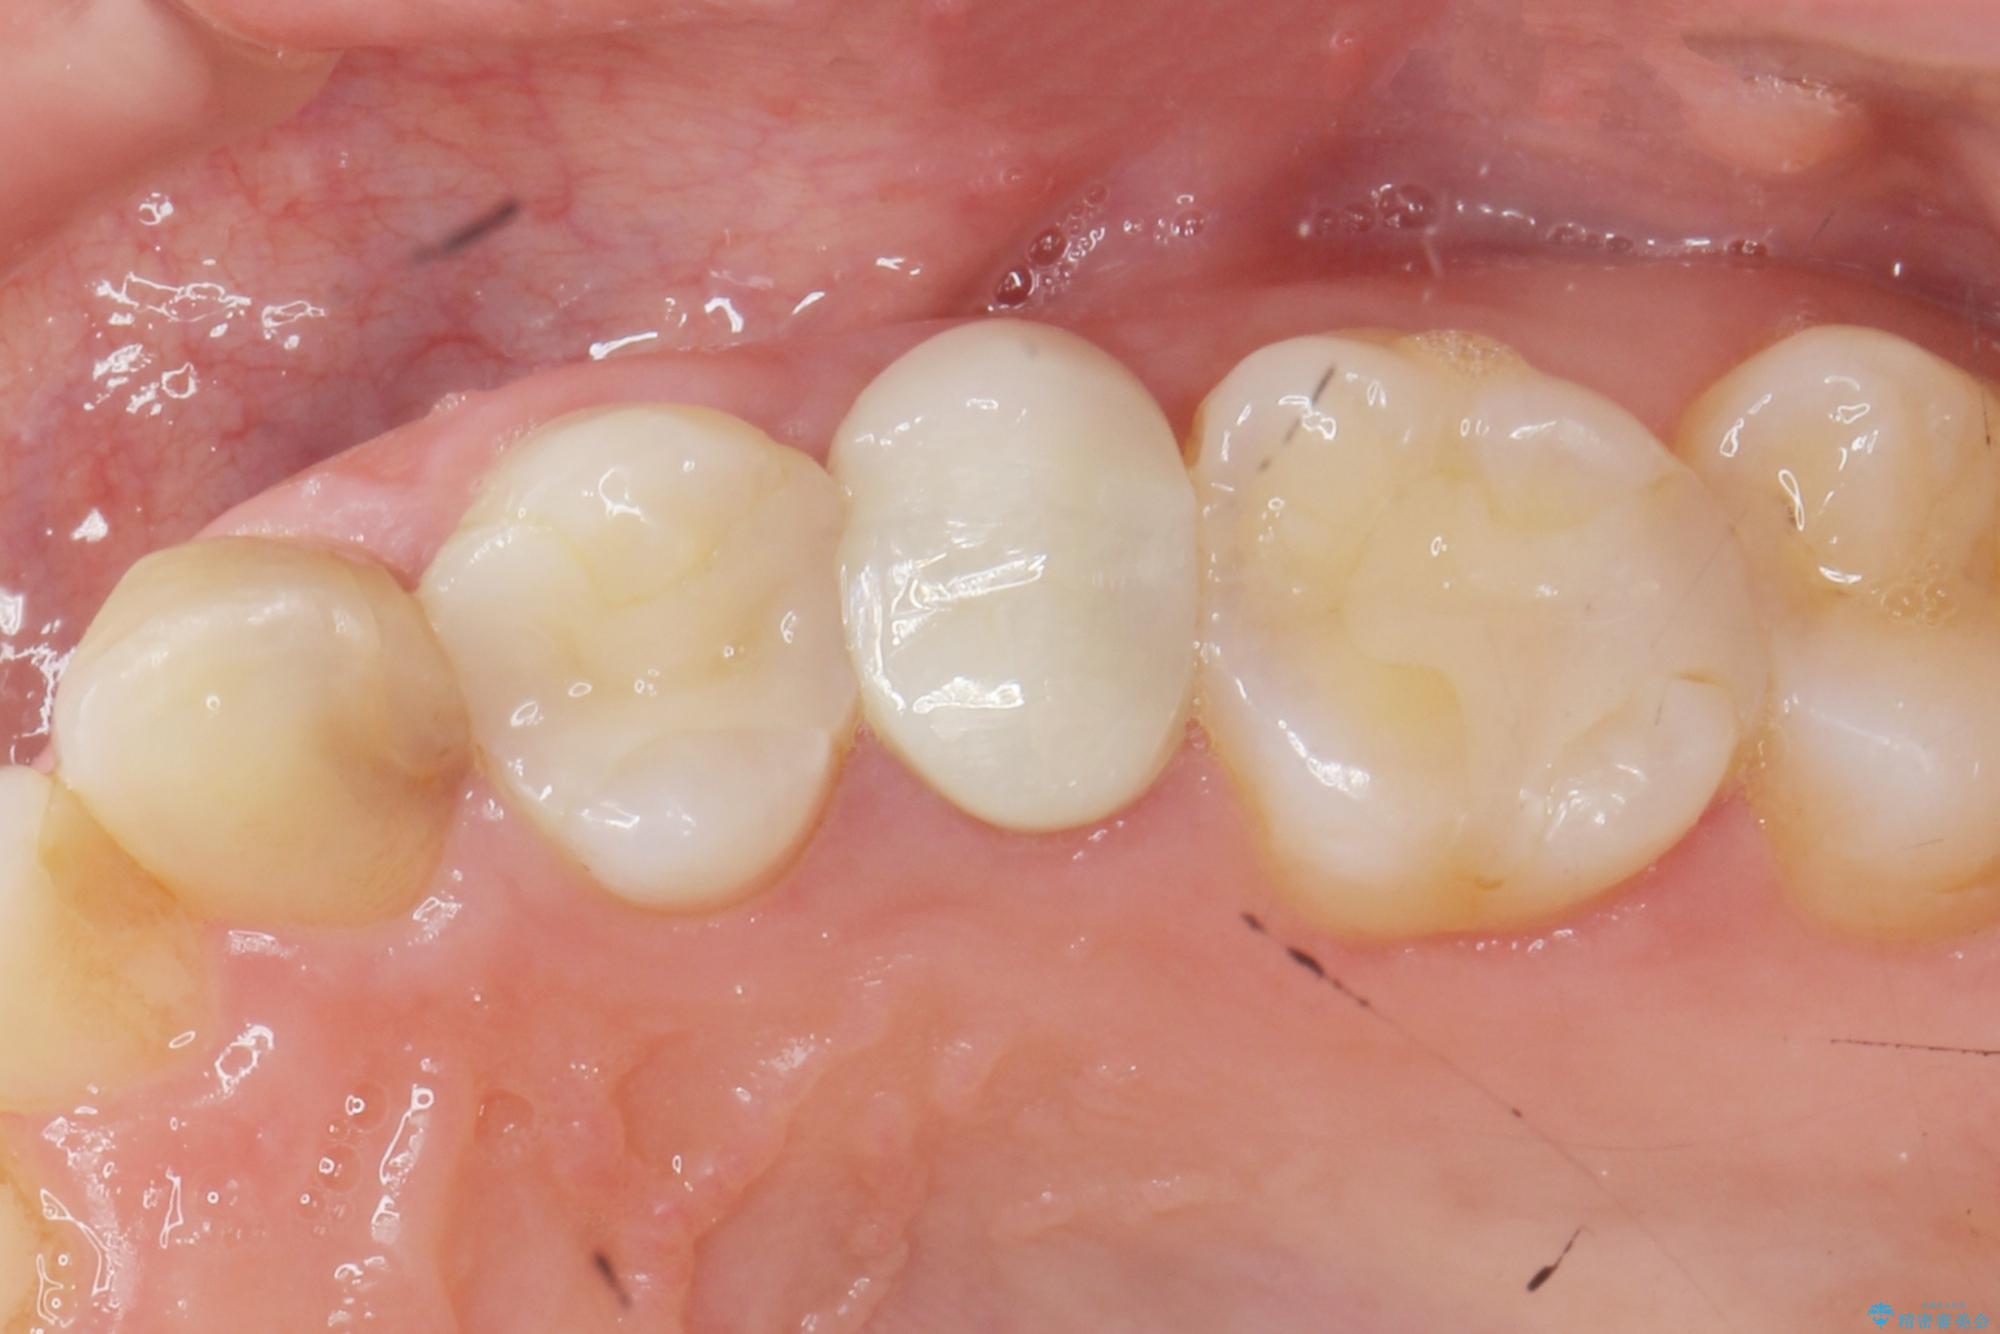

- 歯ぐきの腫れや、歯の内部が黒く見えることからの虫歯の治療を求めて来院されました。

虫歯が大きかったことから、神経の温存はできたものの歯ぐきよりも深い虫歯の問題を解決するため部分矯正治療を併用したセラミック治療を行うこととしました。

当初、歯ぐきよりも深い虫歯のぞんざいや、歯のポジションに問題がありましたがマルチブラケットを用いた部分矯正を行うことで適切な位置へと歯を移動させ、歯周環境を整えたセラミック治療を行うことができました。